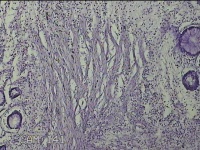

直肠息肉

性别

女

年龄

39岁

临床诊断

混合痔

一般病史

反复肛门肿物3月。

标本名称

大体所见

灰白暗红色条索状肿物5.3x2x0.8cm一个,表面糜烂,切面灰白暗红色,质软。

考虑内痔,伴出血、炎症。